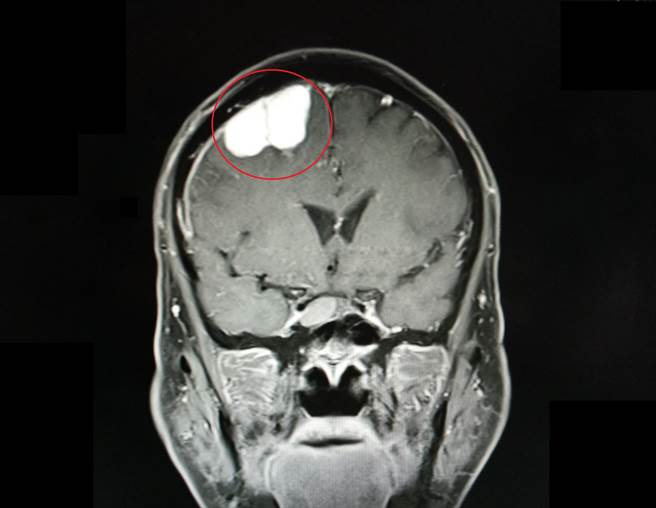

苗栗縣66歲羅姓老翁,有高血壓病史且規則服藥,在家中因走路不穩而跌倒就醫,經核磁共振檢查後,竟發現右側大腦運動區有1顆腫瘤。所幸腫瘤僅3公分,位置在腦部表淺位置,且病理報告顯示為良性腦膜瘤,經接受手術治療後,順利恢復出院。

曾威傑說,腦瘤症狀包含顱內壓增高引發頭痛、嘔吐、視覺障礙、意識障礙、癲癇、神經功能障礙、一側肢體無力、走路不穩、語言困難、人格變化、內分泌功能障礙。醫師會透過頭部X光、電腦斷層、核磁共振或血管攝影等檢查來確認腦瘤的性質與週邊組織的狀況,以安排後續治療。